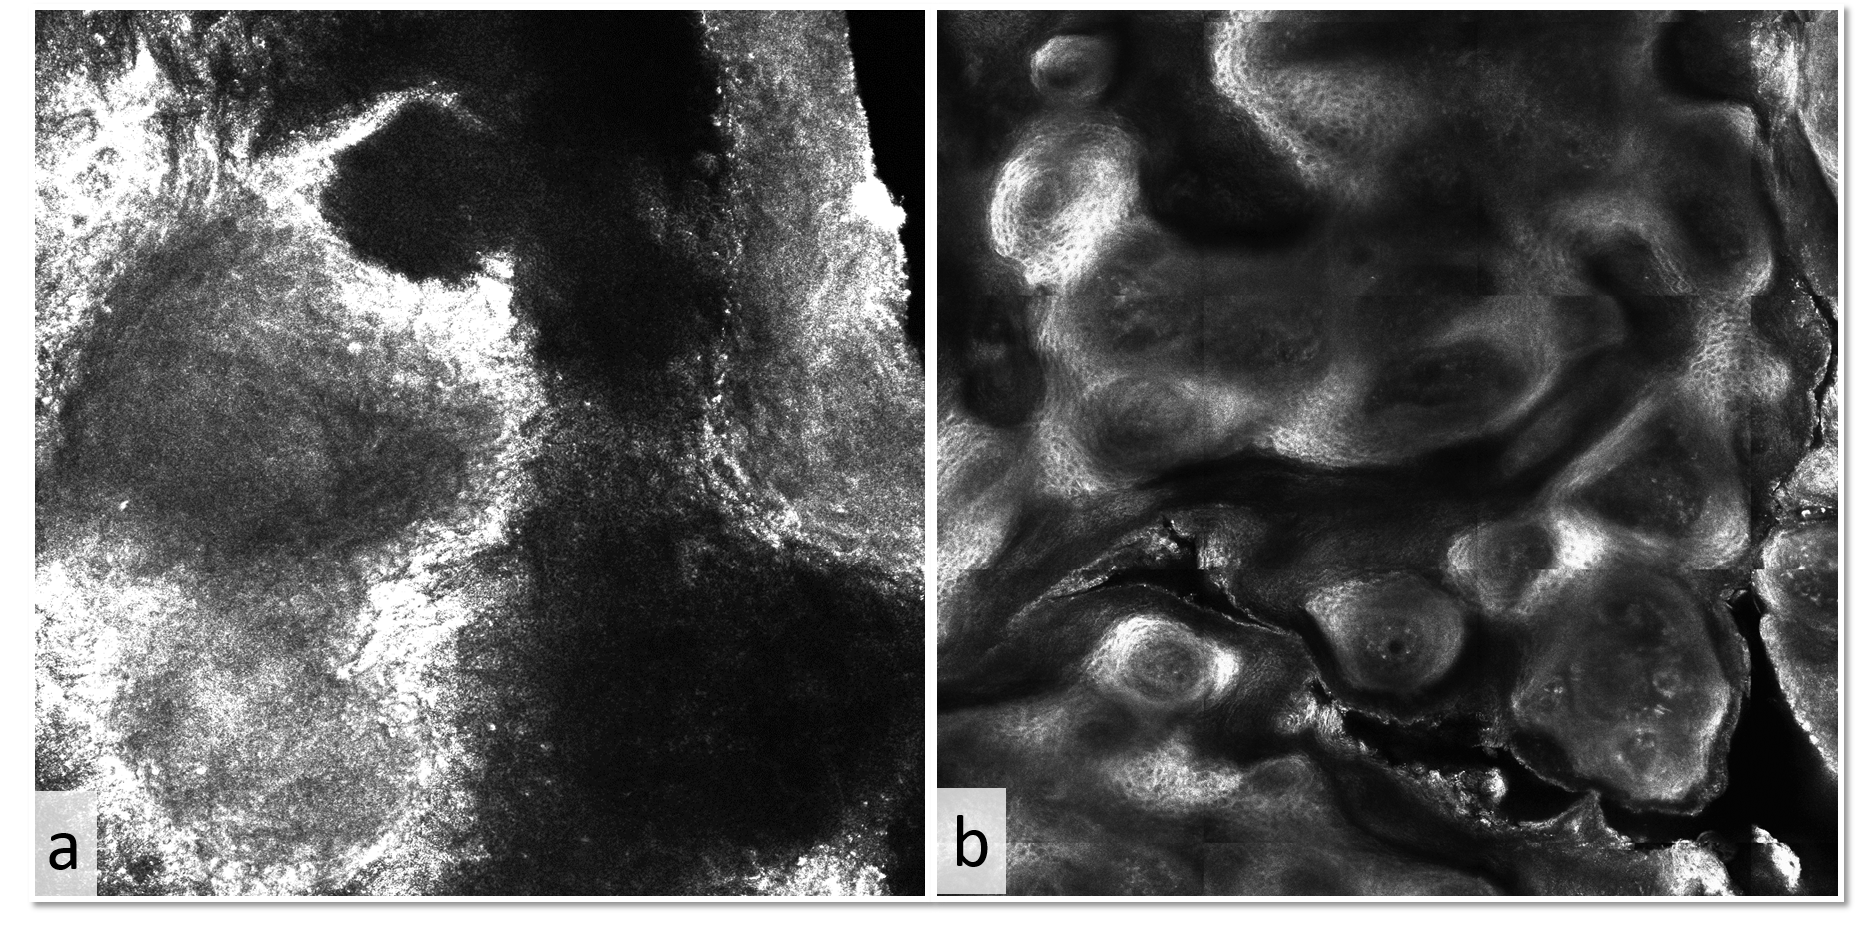

Cutaneous leishmaniasis may mimic other infections in overlapping endemic areas and timely treatment prevents dissemination of the parasite. The required histopathological and microbiological examinations are not always available, and can only give a deferred confirmation of the diagnosis. In contrast, reflectance confocal microscopy (RCM) allows real-time visualization till the level of papillary dermis. A 59-year-old Brazilian male presented with ulcerated plaques and tumors on the extremities. The clinical differential diagnosis included leishmaniasis and other infections with lymphocutaneous pattern of dissemination. RCM showed the characteristic picture of «eggs in a bird’s nest» which has been described in cutaneous leishmaniasis. The diagnosis of leishmaniasis was later confirmed by skin biopsy, in which Leishmania guyanensis was identified by parasitological examination. After treatment with liposomal amphotericin B, reassessment with RCM corroborated the clinical cure, showing an «empty nest» picture. In conclusion, RCM noninvasively provides useful information for diagnosis and follow-up of cutaneous leishmaniasis.